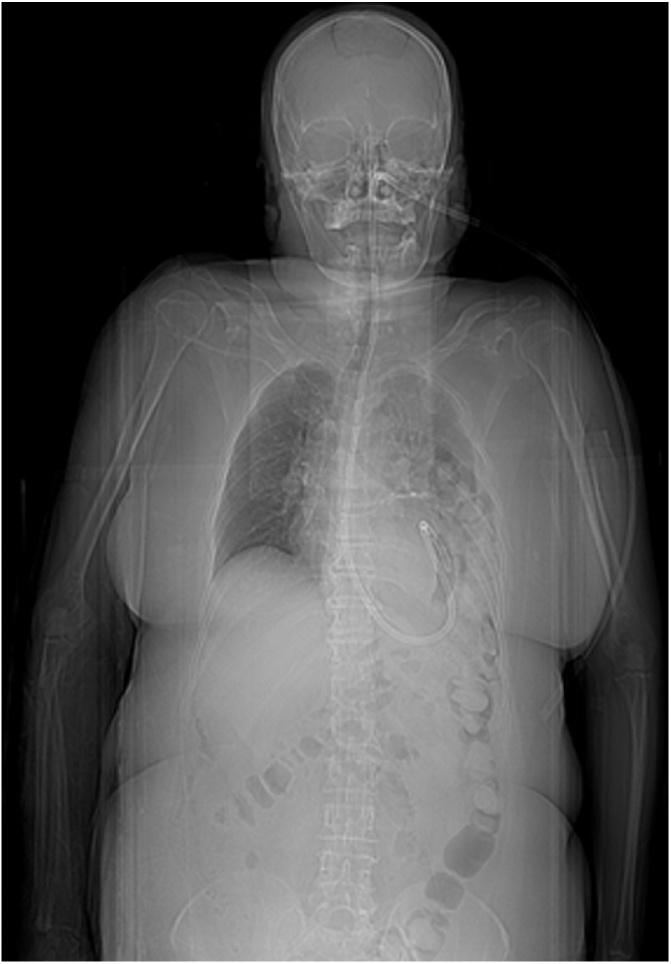

A 62-years old woman was admitted in Emergency Department after a pedestrian accident. A whole-body CT scan showed multiple fractures (ribs, pelvic and vertebral) but no organ injury. The next CT detected a left-sided posterior diaphragmatic hernia involving transverse colon. Thus we performed an explorative laparoscopy and found a double diaphragmatic injury. A primary repair with non-absorbable sutures and a prosthetic titanized patch was performed.

一名62岁女性在行人事故后被送往急诊科。全身CT扫描显示多处骨折(肋骨、骨盆和椎骨),但无器官损伤。随后的CT检查发现左侧后膈疝,累及横结肠。因此,我们进行了探索性腹腔镜检查,发现了双侧膈肌损伤。采用不可吸收缝线进行一期修复,并使用钛化人工补片。